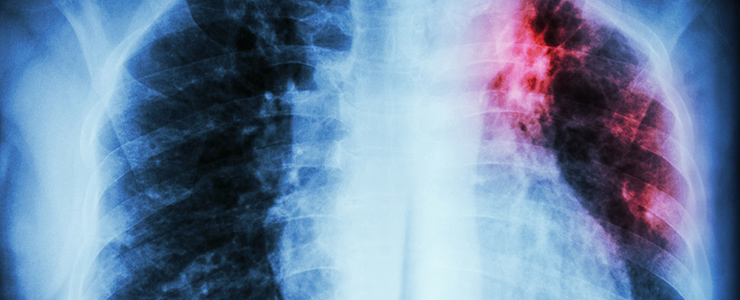

検査方法も進んでいて、人間ドックで一緒に受けられる肺のX線検査や痰などの菌の検査で感染の確認はすぐにできますし、身体に負担もかかりません。